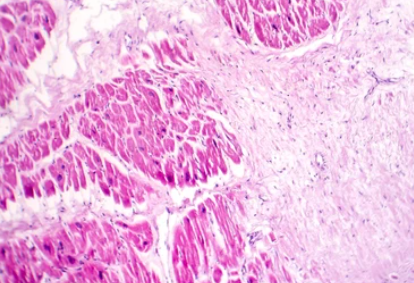

협심증은 관상동맥이 좁아져 발생하는 흉부 통증이라면, 심근경색은 관상동맥이 완전히 막혀 심장근육이 괴사 하면서 발생하는 가슴통증입니다. 따라서 협심증 환자 중 일부는 흉통 없이 호흡곤란만을 호소하기도 한다고 하네요.